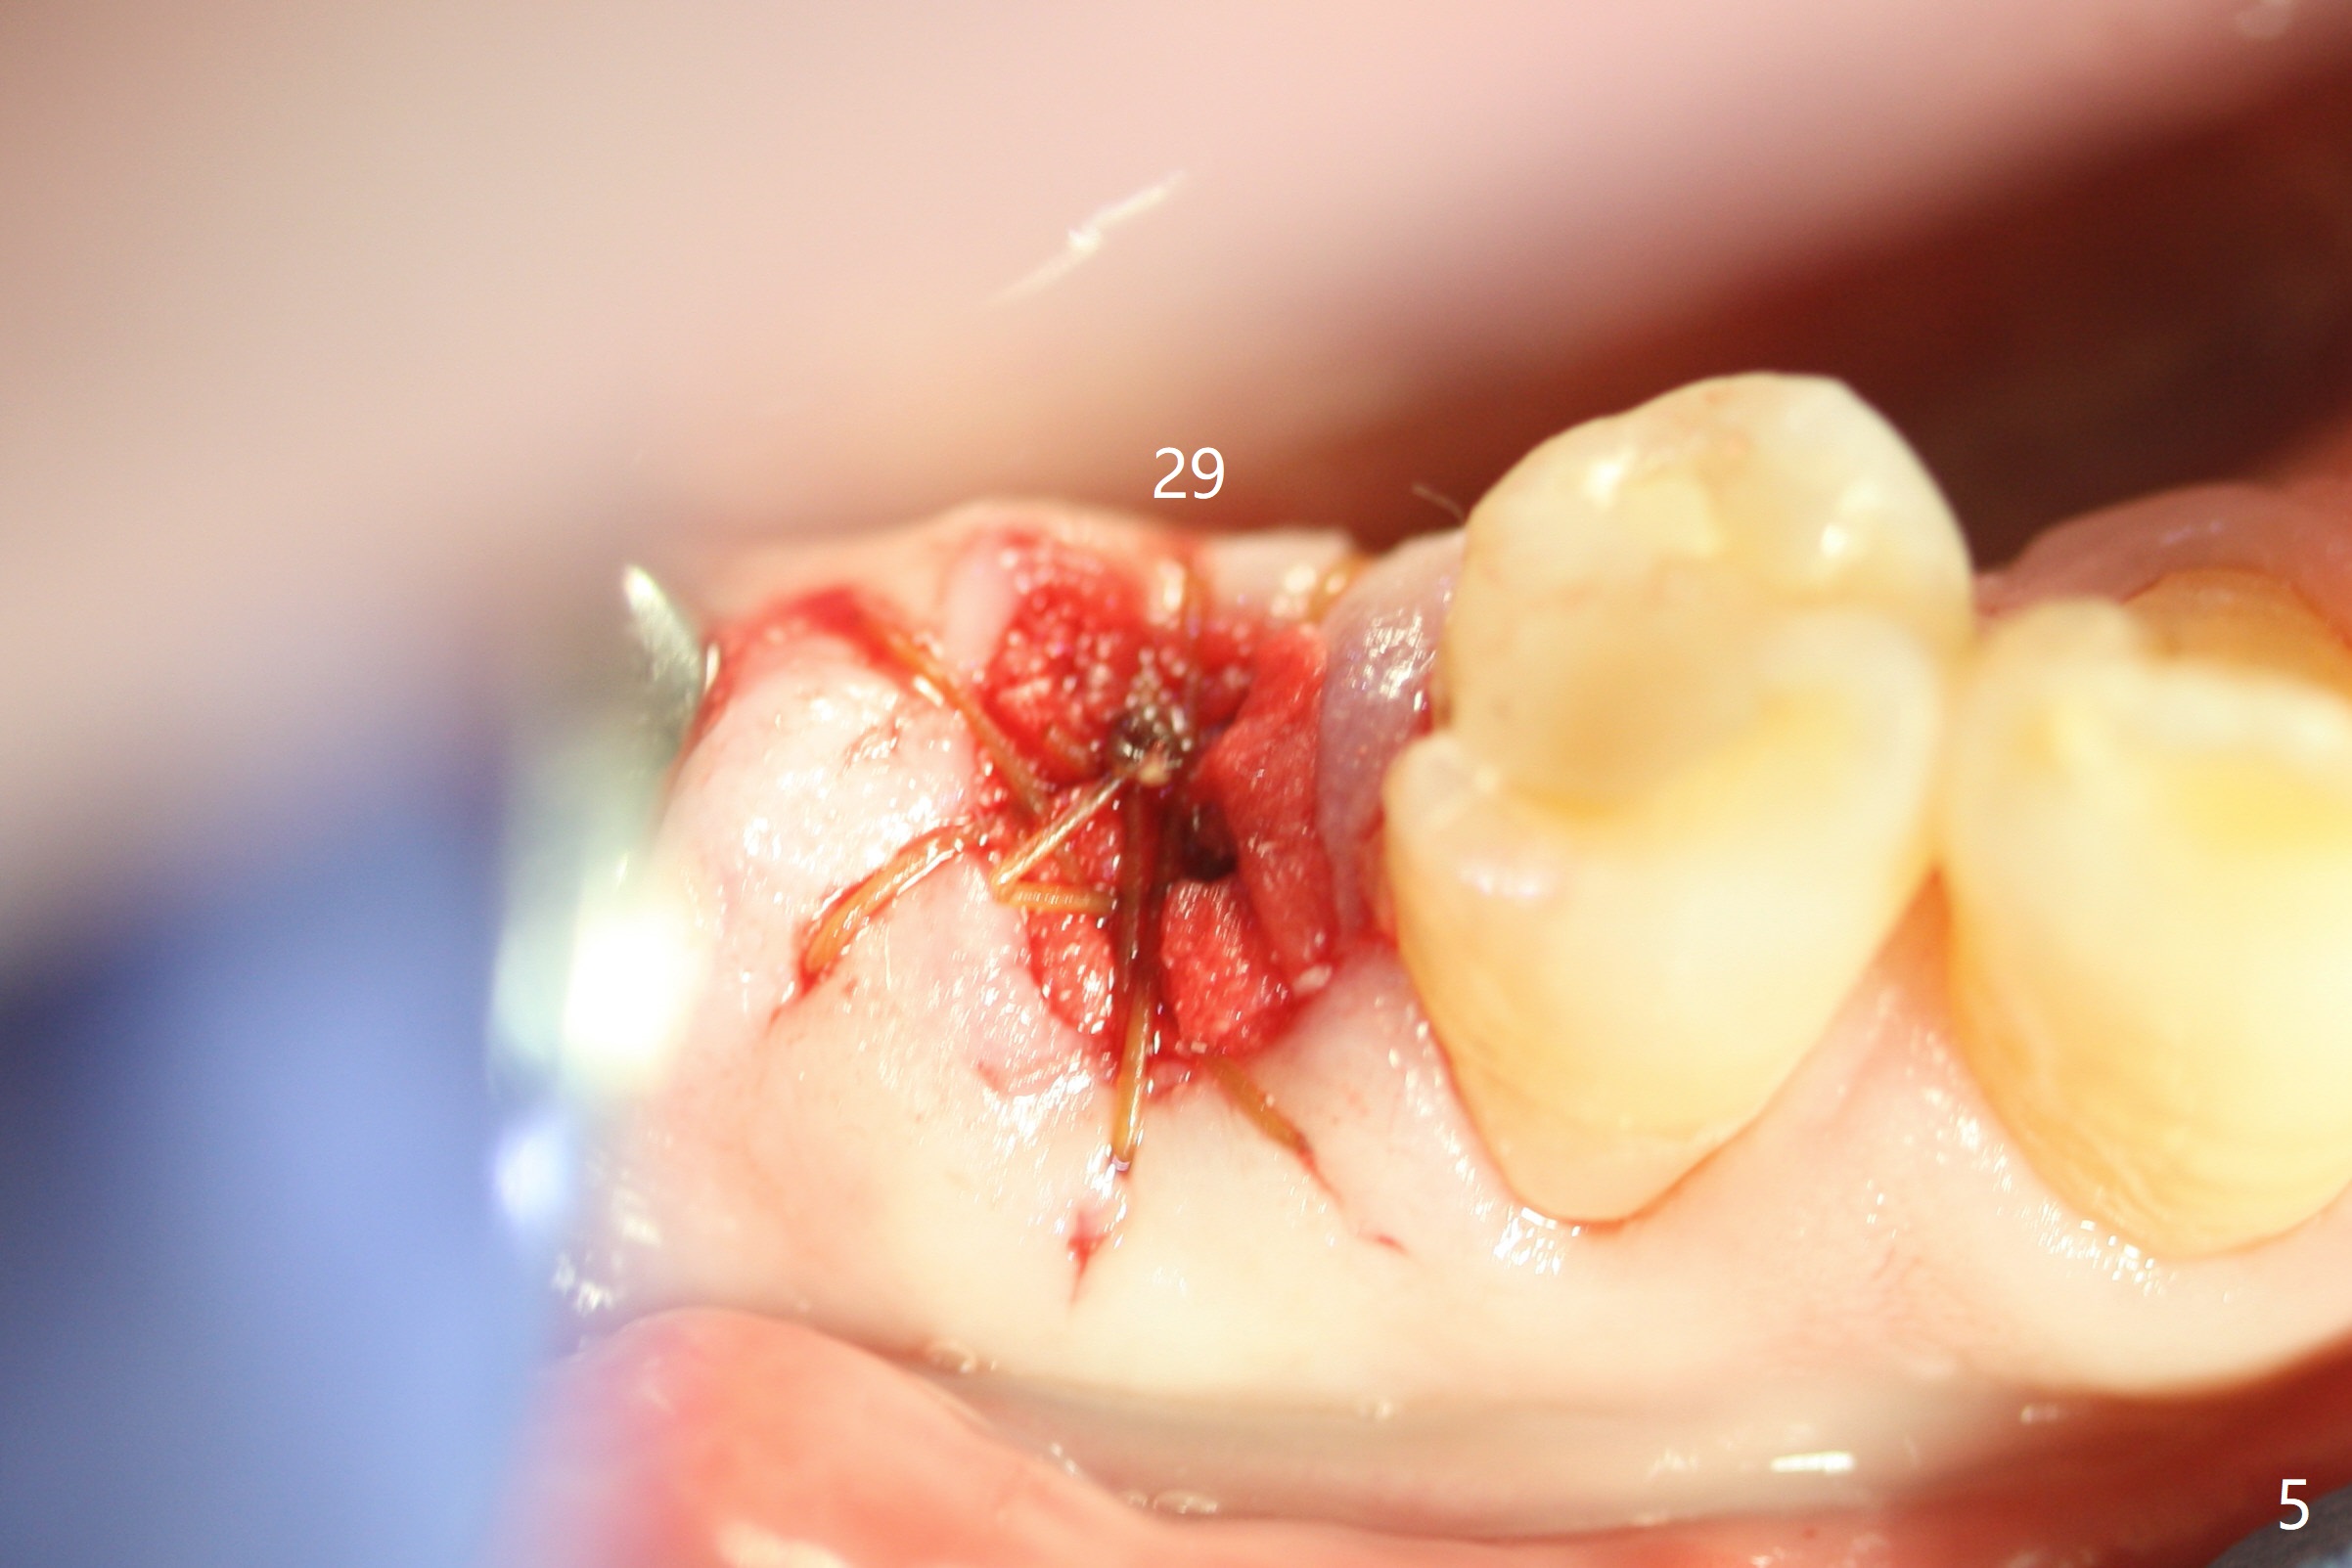

The patient is hesitant about apicoectomy. After discussion of advantages and disadvantages of the latter vs. extraction and implant, the patient chooses the extraction. The latter turns out to be smooth with socket preservation (Fig.4, 5 *). Immediately postop PA shows bone loss at #30 and minor degree around the apex of #31 implant (Fig.4 <), which is probably related with hard bone and bone necrosis due to heat.